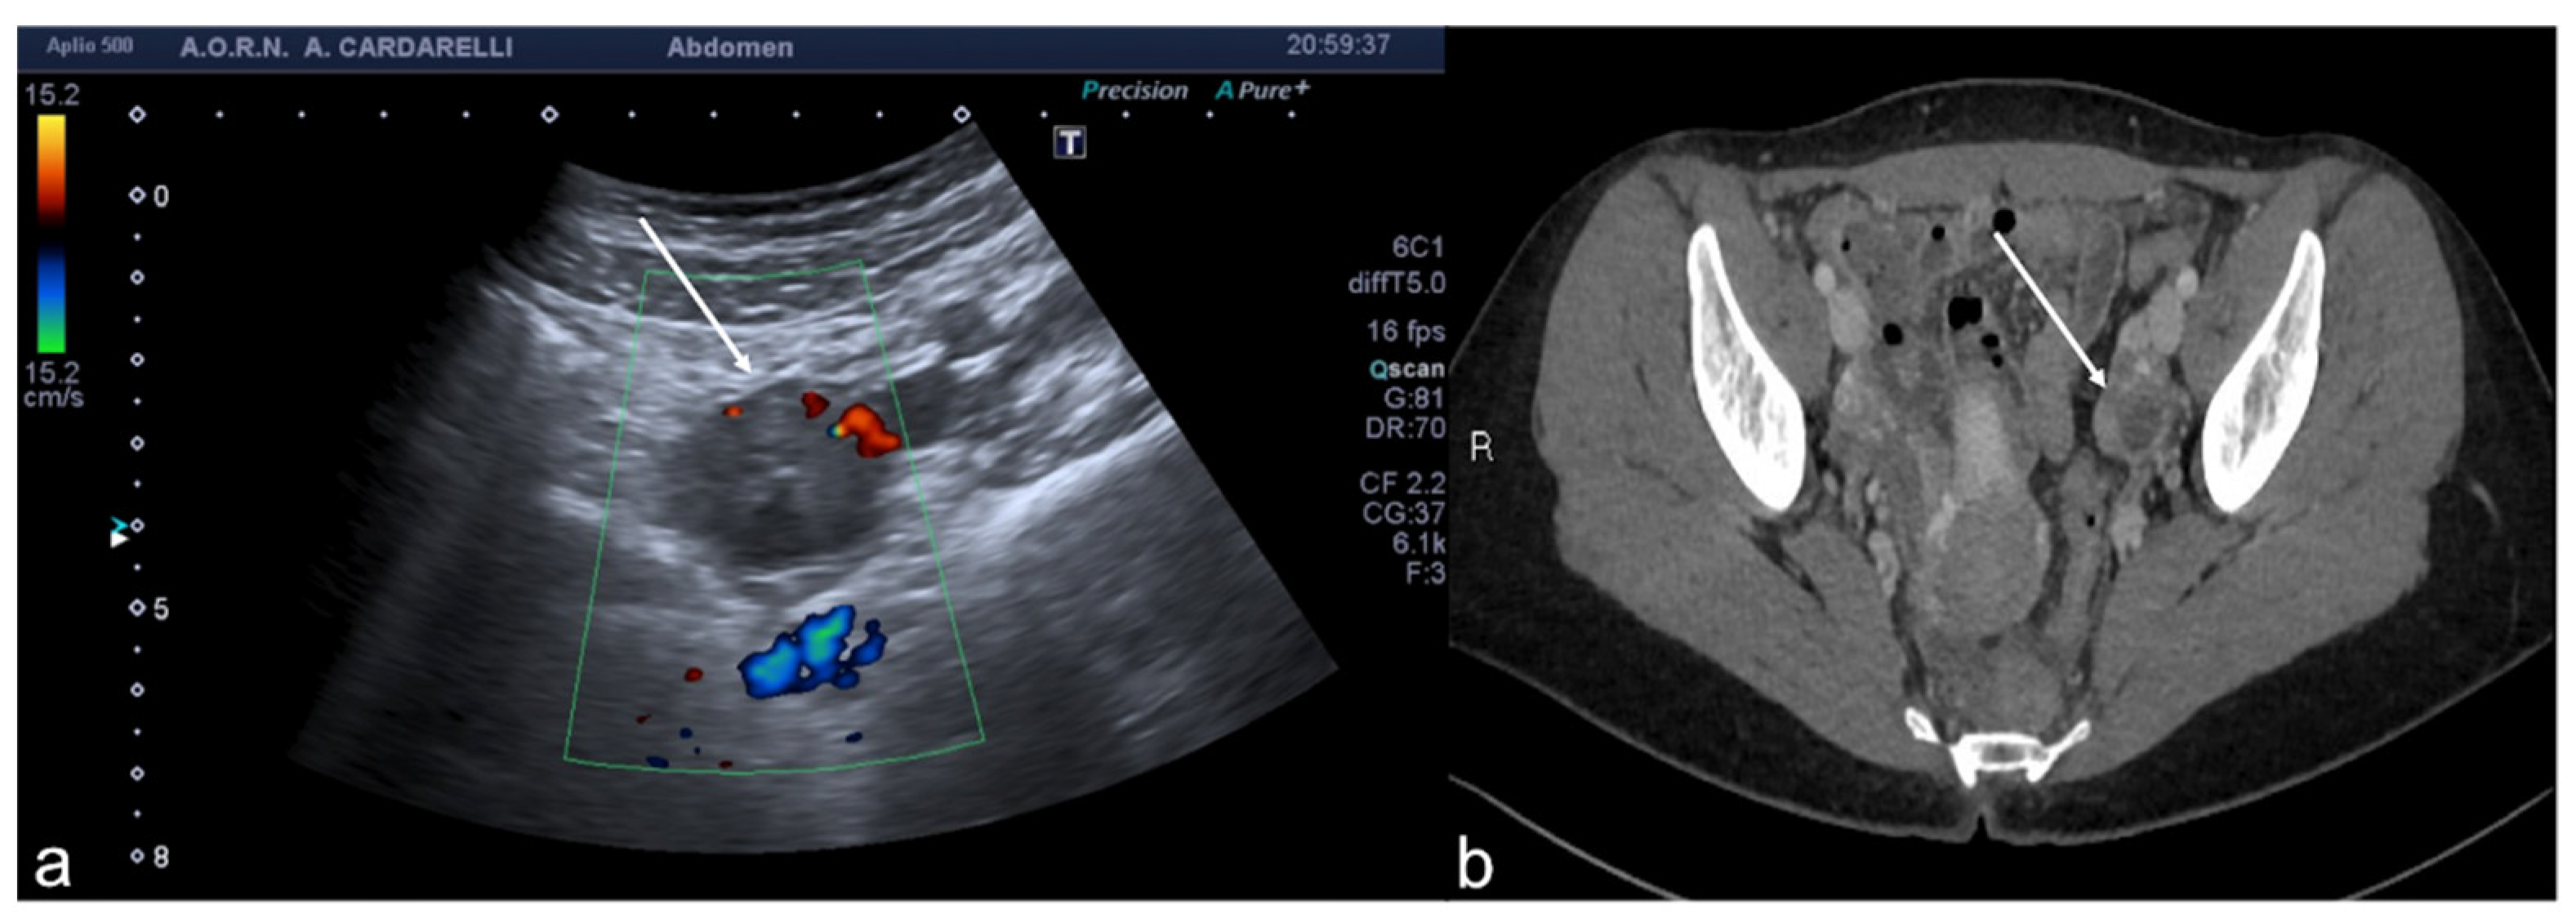

Figure 6. Tubo-ovarian complex. Axial colour-Doppler TSA–US scan of the left adnexa (a) shows a complex cystic mass with peripheral signal colour Doppler ((a) arrow). Contrast-enhanced axial CT image (b) shows a thick enhancing left adnexa abscess wall ((b) arrows).